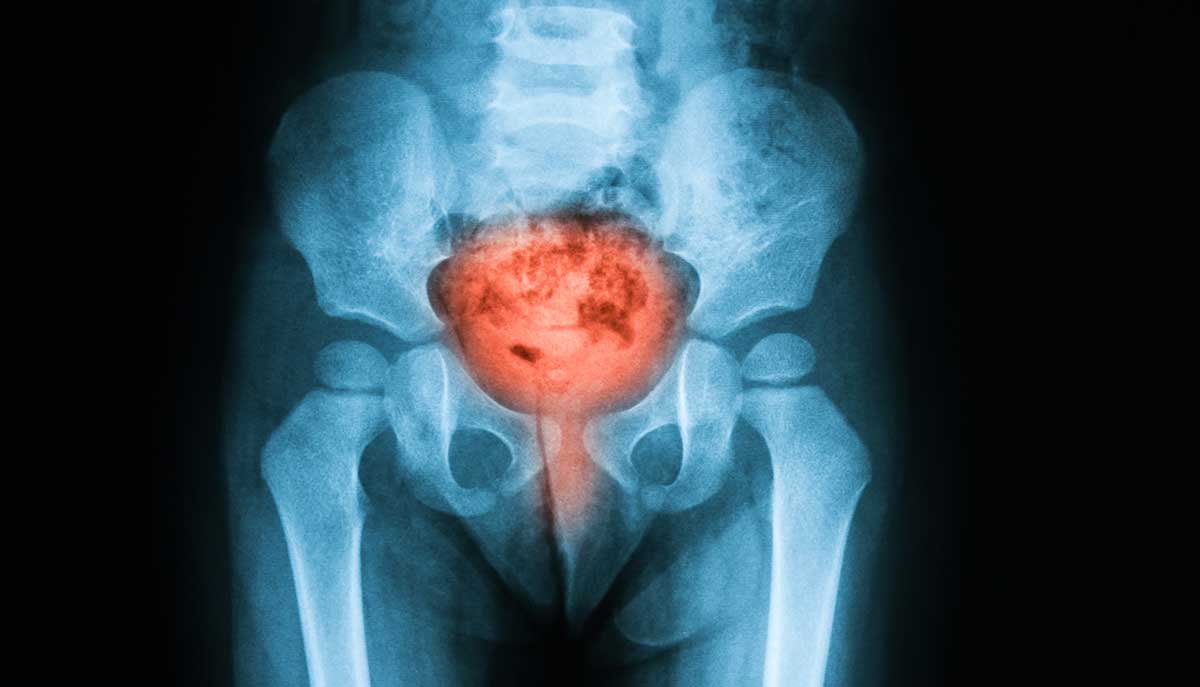

Στον εν λόγω καρκίνο σχηματίζονται κακοήθη (καρκινικά) κύτταρα στους ιστούς της ουροδόχου κύστης.

Η ουροδόχος κύστη είναι ένα κοίλο όργανο στο κάτω μέρος της κοιλιάς. Έχει σχήμα μικρού μπαλονιού και έχει ένα μυϊκό τοίχωμα που του επιτρέπει να γίνεται μεγαλύτερο ή μικρότερο για να αποθηκεύει τα ούρα που παράγονται από τους νεφρούς.

Υπάρχουν δύο νεφροί, ένας σε κάθε πλευρά της σπονδυλικής στήλης, πάνω από την μέση. Μικροσκοπικά σωληνάρια στους νεφρούς φιλτράρουν και καθαρίζουν το αίμα. Βγάζουν τα απόβλητα και παράγουν ούρα. Τα ούρα περνούν από κάθε νεφρό μέσω ενός μακρύ σωλήνα (ουρητήρας) στην ουροδόχο κύστη. Η κύστη συγκρατεί τα ούρα μέχρι να περάσουν από την ουρήθρα και να φύγουν από το σώμα.